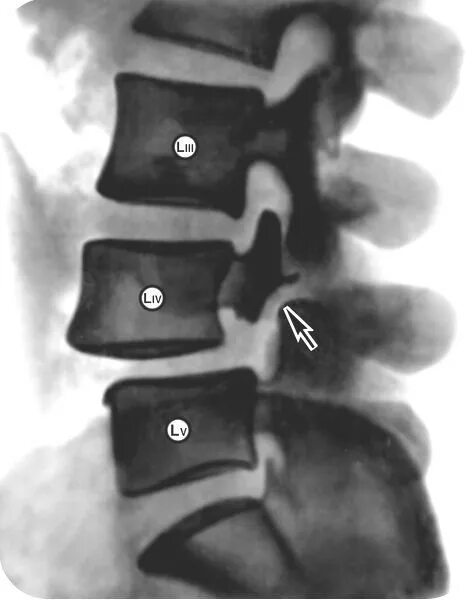

Смещение позвонков поясничного операция